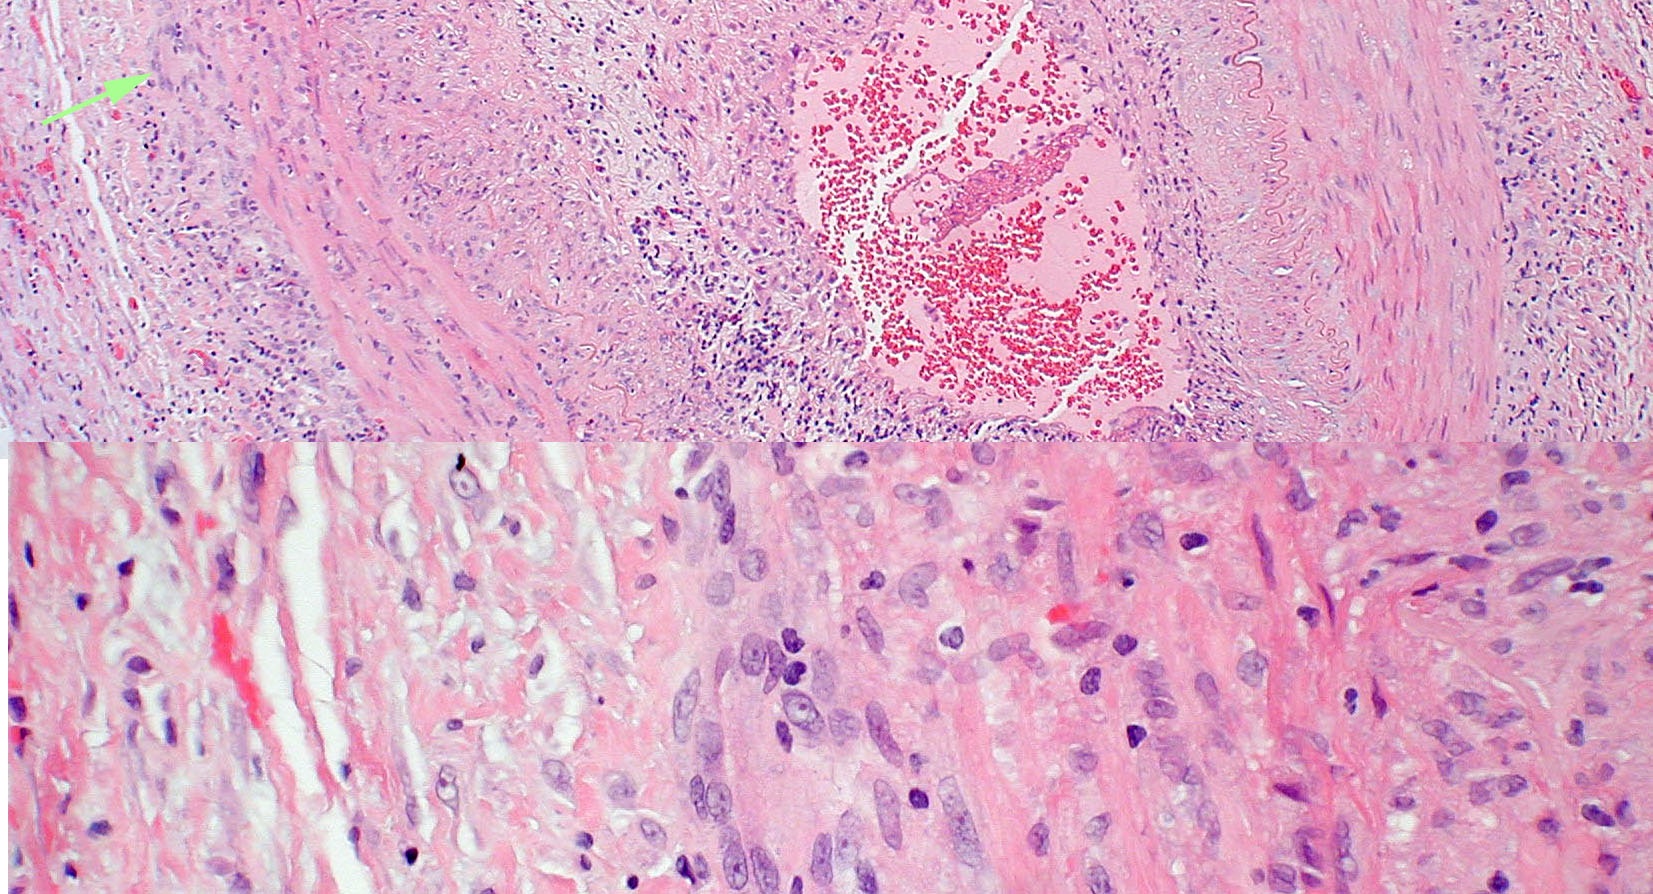

Pathologic specimen from a patient with biopsy proven giant cell arteritis. Multi-nucleated giant cells (arrow) are present in the vessel wall. Photograph courtesy of Ben Glasgow, M.D.

| current | 10:32, July 2, 2010 | 1,653 × 894 (604 KB) | Stacy.l.pineles.cmt (talk | contribs) | Pathologic specimen from a patient with biopsy proven giant cell arteritis. Multi-nucleated giant cells (arrow) are present in the vessel wall. Photograph courtesy of Ben Glasgow, M.D. |